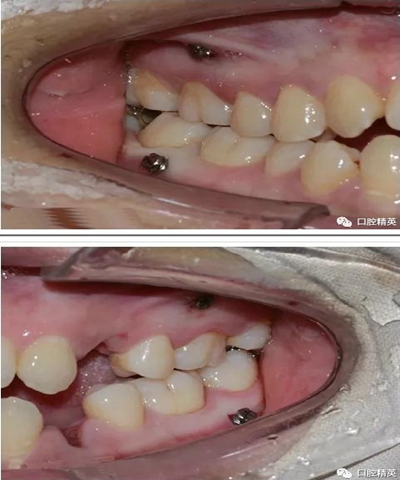

微型種植釘直徑僅有1.6mm和2mm,植入部位幾乎可以不受限制,可植入牙槽骨的任何部位,微型種植體支抗植入手術(shù)操作簡(jiǎn)單、安全,不需要牙齦翻瓣,即可旋入微型種植體,整個(gè)手術(shù)過(guò)程僅需5-10min,術(shù)后患者的不良反應(yīng)少,微型種植體的取出亦非常簡(jiǎn)單,甚至不需局部麻醉,將其反向旋出即可。自攻型種植釘植入牙槽骨中起支抗作用.

一般情況下是成年人使用,特殊病例十三、四歲的小孩可以用。種植釘可以打在牙槽骨的任何部位??梢栽?個(gè)牙齒之間的牙槽骨上打釘,或者打在頰側(cè)牙槽骨與牙根之間,主要看你是如何應(yīng)用支抗了。2個(gè)牙齒之間的牙槽骨上打釘,支抗作用拉動(dòng)的牙齒有限,而打在頰側(cè)牙槽骨與牙根之間可以將整個(gè)牙列拉向遠(yuǎn)中移動(dòng)。種植支抗釘在矯正結(jié)束后要拿下來(lái)。

再次,植入微型種植體,在附著牙齦處不需要粘骨膜翻瓣,在牙槽黏膜處則需要切開(kāi)黏膜以避免植入時(shí)軟組織被卷入,植入部位通常在膜齦結(jié)合部位或偏根方2~3mm,植入角度與骨面垂直并傾斜15~20度,即向根尖方向植入,術(shù)后拍根尖片以確認(rèn)與牙根的關(guān)系。術(shù)后口服抗生素預(yù)防感染并進(jìn)行口腔衛(wèi)生宣教。

上頜種植釘?shù)闹睆?.6,長(zhǎng)度11mm;下頜直徑2.0,長(zhǎng)度9mm

1、上頜種植釘常見(jiàn)位置在5,6之間;下頜種植釘常見(jiàn)位置在6,7之間。